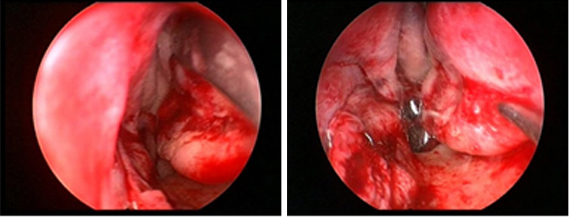

Keystone 보존 휜코 교정법은 keystone을 손상 시키지 않고 휜코 교정이 가능합니다.

휜코의 경우 좌우 코뼈에서 한 쪽은 절골만 시행하고 다른 한 쪽은 뼈 일부를 절제한 후,

절제한 쪽으로 밀어주면 연골도 같이 움직이기 때문에 keystone을 전혀 건드리지 않고도 교정이 가능합니다.

이로 인해 연골이식(쐐기이식)도 필요 없거나 또는 최소한으로만 사용되며

콧대의 굴곡을 피할 수 있고, 기존의 휜코 교정보다도 안정적이며 결과도 훨씬 좋습니다.

이 수술방법은 고가의 장비인 첨단 초음파 절골장비(piezotome)와 코 내시경이 필요하며

의사의 노하우가 필요하기 때문에 관련된 임상 경험을 풍부히 갖추고 있는

숙련된 의료진에게 받는 것이 중요합니다.